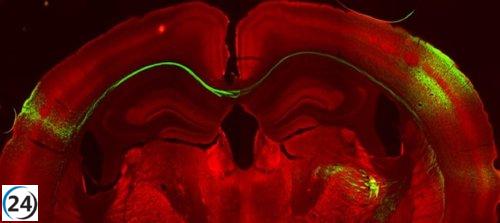

Nuevo estudio revela cómo se transmiten los estímulos sensoriales entre los hemisferios cerebrales

30/11/2023